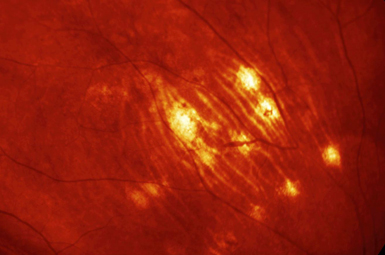

Image courtesy of Heidelberg Engineering, Inc.

Intermediate Uveitis

Intermediate Uveitis occurs when inflammation involves only the vitreous. Causes include Pars Planitis, and numerous infectious and inflammatory etiologies.

Posterior Uveitis

This represents Chorioretinal inflammation. It is caused by numerous types of infection and inflammation, and frequently requires medical therapy.

Pan-Uveitis

Pan-Uveitis represents inflammation of all eye layers. It requires a full evaluation, and frequently requires medical treatment and immunosuppression.